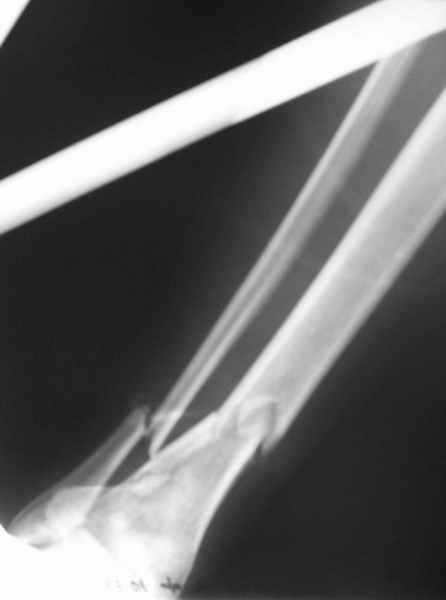

Открытый оскольчатый перелом н/3 голени.

Здравствуйте, коллеги! 16/10/06 г. В отделение поступила больная с производственной травмой - Открытый оскольчатый перелом метафиза и метадиафиза обеих костей правой голени со смещением отлоков.

Здравствуйте коллеги! В данной ситуации я полностью согласен с мнением Александра Николаевича! Практически любой внутрисуставной(тем более приведенный на снимках) перелом требует открытой репозиции.Судя по приведенным рентгенограммам, в области дистального тибио-фибулярного сочленения имеется "минус" ткань на tibia, которая может потребовать костной пластики.Метод фиксации любой,главное ранние движения в суставе. С уважением Руслан Ш.

К слову, тема этого обсуждения обозначена неточно, тут перелом дистального суставного конца типа 43-C, а не "открытый оскольчатый перелом н/3 голени", т.е. диафизарный, 42-.

Действительно, речь идет о сложном внутрисуставном, да еще и открытом переломе 43С.3.

1. Представленные рентгенограммы во-превых плохого качества (ну да ерунда), а во-вторых (самое главное) - в нестандартных проекциях. Невозможно оценить количество и положение фрагментов суставной поврехности. Собственно это делает обсуждение бессмысленным. Мы обсуждаем не конкретный случай, а вообще...